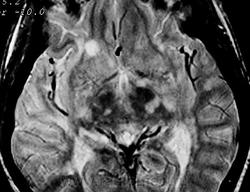

ГМ. Рассеянный склероз 3. +

Рассеянный склероз